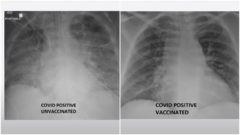

Rozdiel v snímke pľúc zaočkovaného a nezaočkovaného pacienta je diametrálny. Nakazili sa obaja, len jeden je však na tom zle